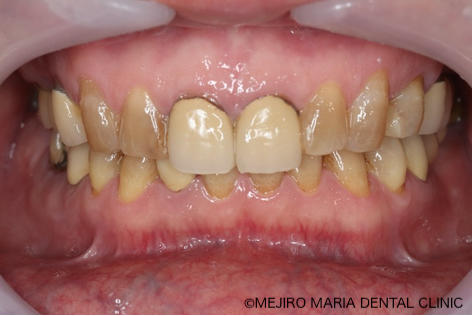

患者様は、長年にわたり臼歯部(奥歯)の噛み合わせの調子が悪いことと、食事の際に痛みを感じることを主訴に来院されました。前歯部から口腔内を確認すると大きなトラブルは確認できませんが、レントゲン撮影と口腔内診査を行うと、多数の臼歯部の歯牙(歯)が歯根破折により抜歯を余儀なくされる状況でした。

今回の症例では、歯根破折していた5本の歯牙(下の写真・赤矢印)に対して、抜歯を提案した。また、診断用WaxUp(ワックスアップ)を行ったところ左下のブリッジ(青丸)と右下(青矢印)の噛み合わせ平面が乱れており、咬合に負担をかけていることが予想されました。そのため、最終的にそれらの不調和を改善し、適切な噛み合わせにすることをゴールとして治療を開始しました。